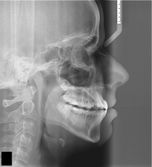

The changes that occur in the morphology of the cervical vertebrae C2, C3 and C4, present in routine lateral cephalograms can be used in the evaluation of bone maturation, in a reliable way and with the same clinical value of the assessment of the hand and wrist region.

Easy Age calculates bone age by the following methods:

- Hassel & Farman (1995)

- Mito et al (2002)

- Baccetti et al (2005)